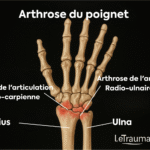

Arthrose du poignet

L’arthrose résulte de l’usure du cartilage. Elle est souvent secondaire à un traumatisme ancien ou à une maladie inflammatoire. Elle provoque :

- douleur mécanique,

- raideur articulaire,

- craquements.